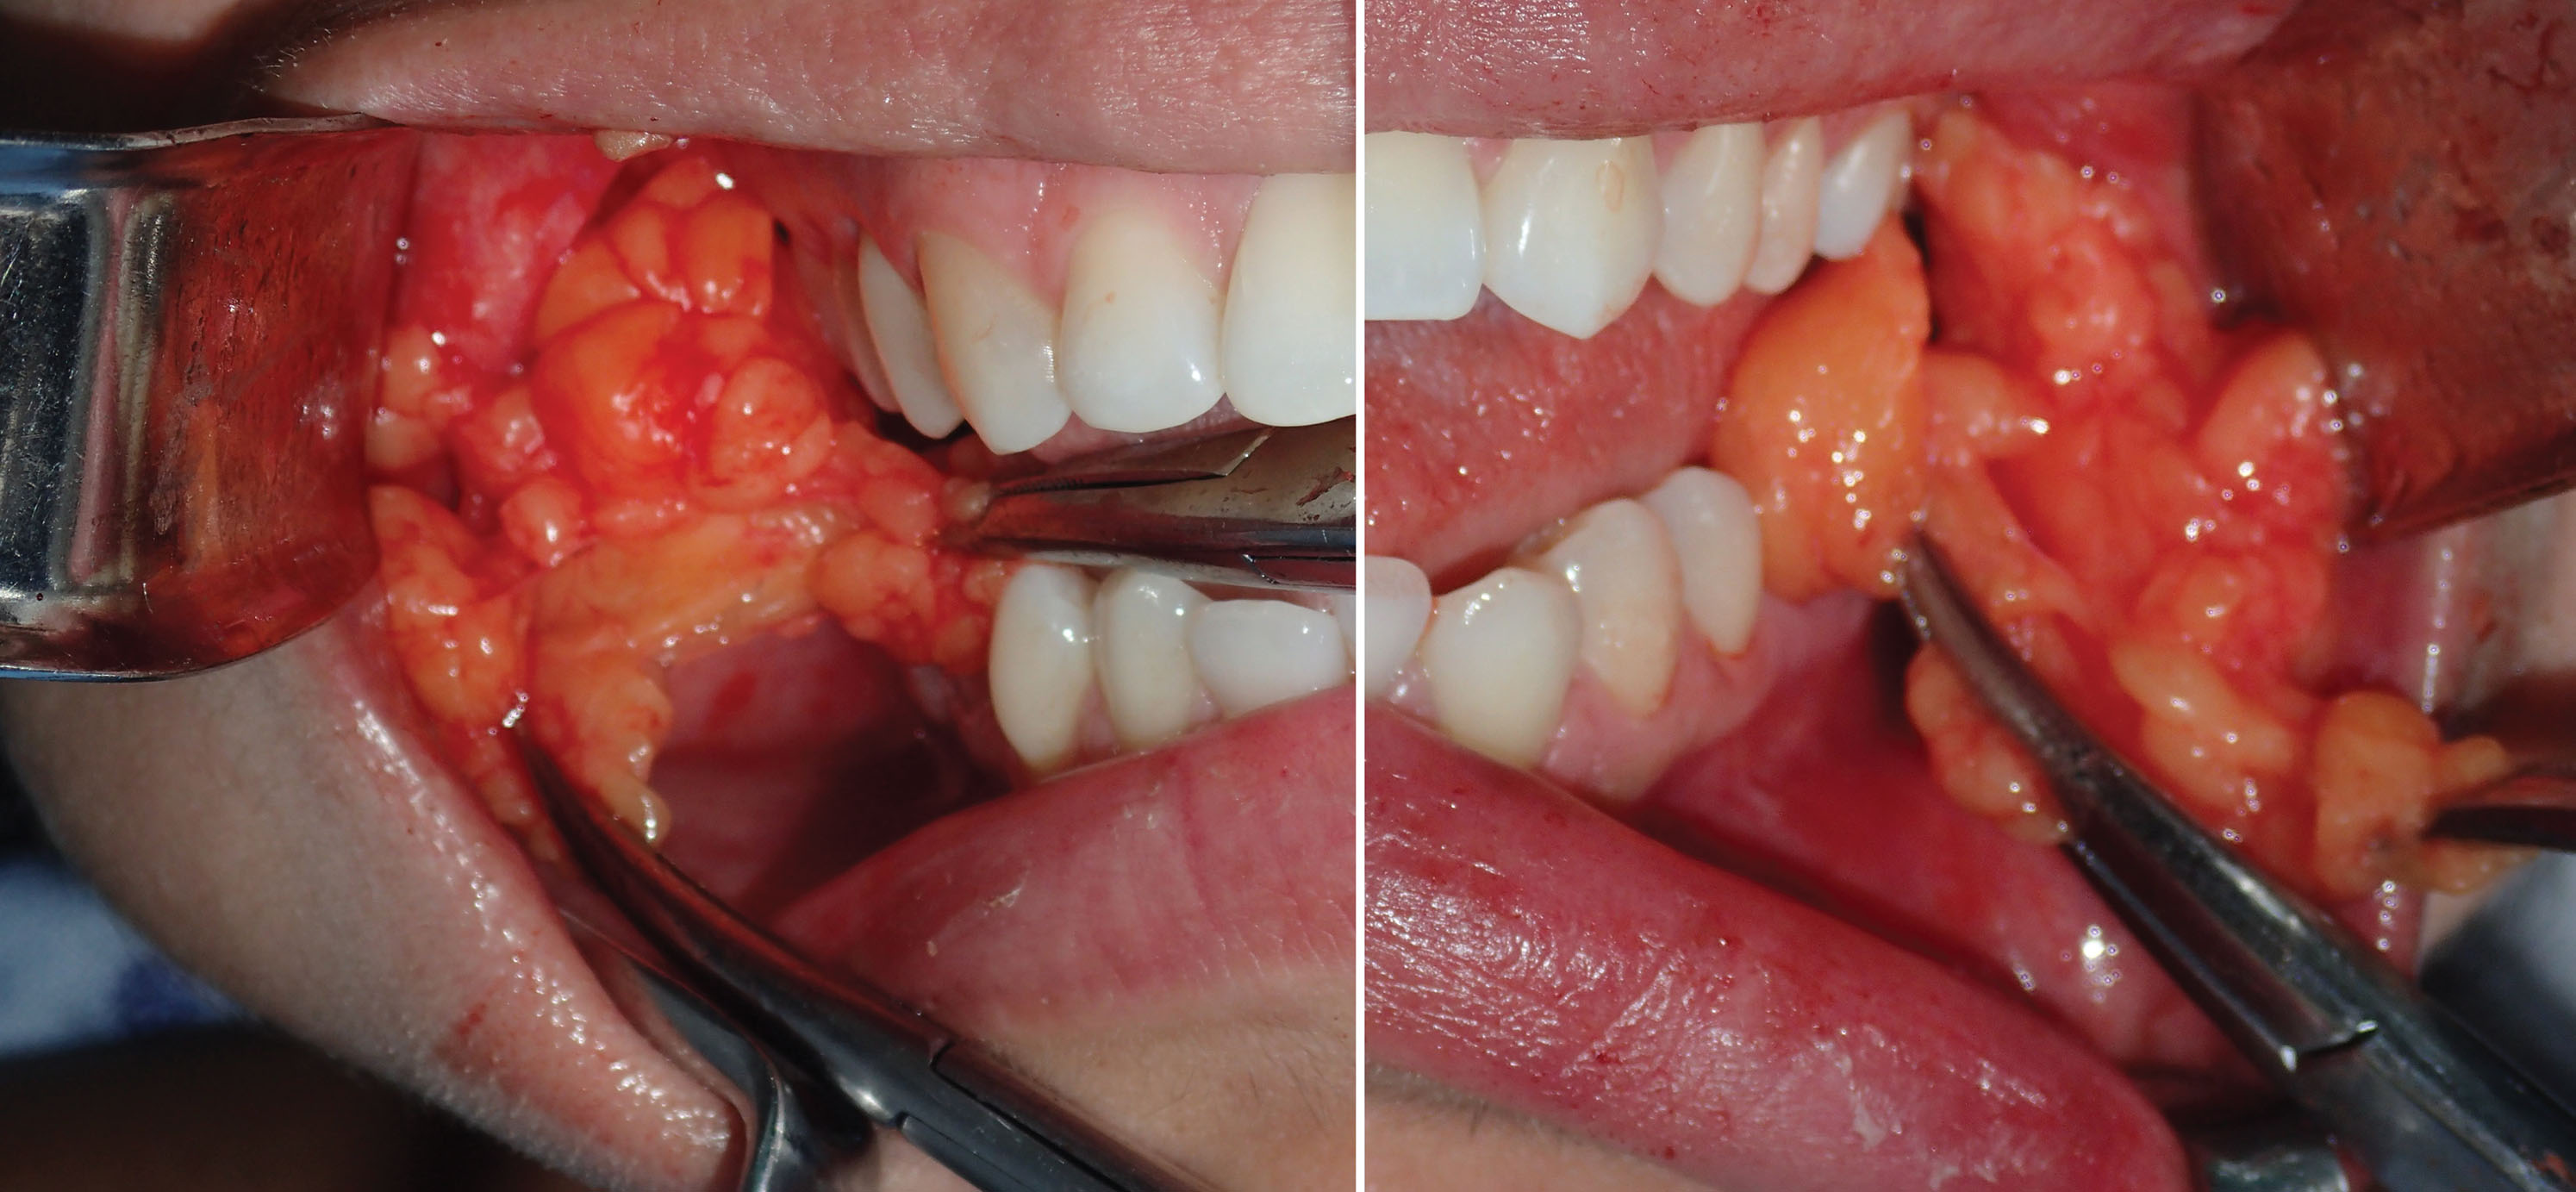

The end point of buccal fat reduction is gauged in a similar manner to blepharoplasty. The excess fat that readily presents itself with minor traction and superficial exploration is removed. Additional contributions to the end point are the lack of additional fat delivered into the mouth and visible depressions at the site of the BFP ( Fig. 15.22 ). Performing BFR is very similar to blepharoplasty in that overresection can produce a skeletonized appearance. Facial fat is a friend and not an enemy, and reduction should be judicious. Generally removing all of the easily available fat that herniates into the oral cavity with suction or moderate traction is sufficient for a noticeable clinical result.

Before transection, a photo is taken of the BFPs when delivered into the mouth. A photo is also taken of the excised specimen ( Figs. 15.23 and 15.24 ). This is done for medical records and also because every single patient is interested in how much fat was removed.

After sufficient fat is removed, the surgical site is checked for hemostasis. The buccinator muscle at the incision site is a frequent source of bleeding and can contribute to a hematoma. If active bleeding is encountered deeper in the wound, cauterization must be carefully addressed as facial nerve branches can be in the proximity as they traverse the masseter muscle. Packing the wound with gauze can also assist in hemostasis. Wound closure is performed with one or two 4-0 gut sutures.